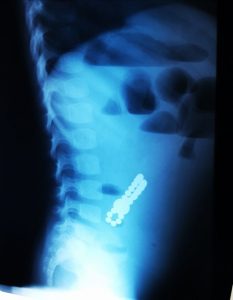

Acești magneți sunt foarte puternici, iar ingestia lor poate duce la probleme gastrointestinale grave. Odată înghițiți sunt atrași unul spre altul chiar dacă se găsesc în secțiuni diferite ale tubului digestiv. O ansă intestinală prinsă între acești magneți se poate perfora ducând la tratament chirurgical de urgență. În secția noastră, de la începutul anului s-au prezentat trei cazuri, două fete și un băiat, cu vârste cuprinse între 2 și 4 ani. Aceștia au suferit perforații la nivelul intestinului subțire și au necesitat intervenții pentru îndepartarea porțiunii de intestin afectate”, a precizat dr. Adriana Constantineanu.